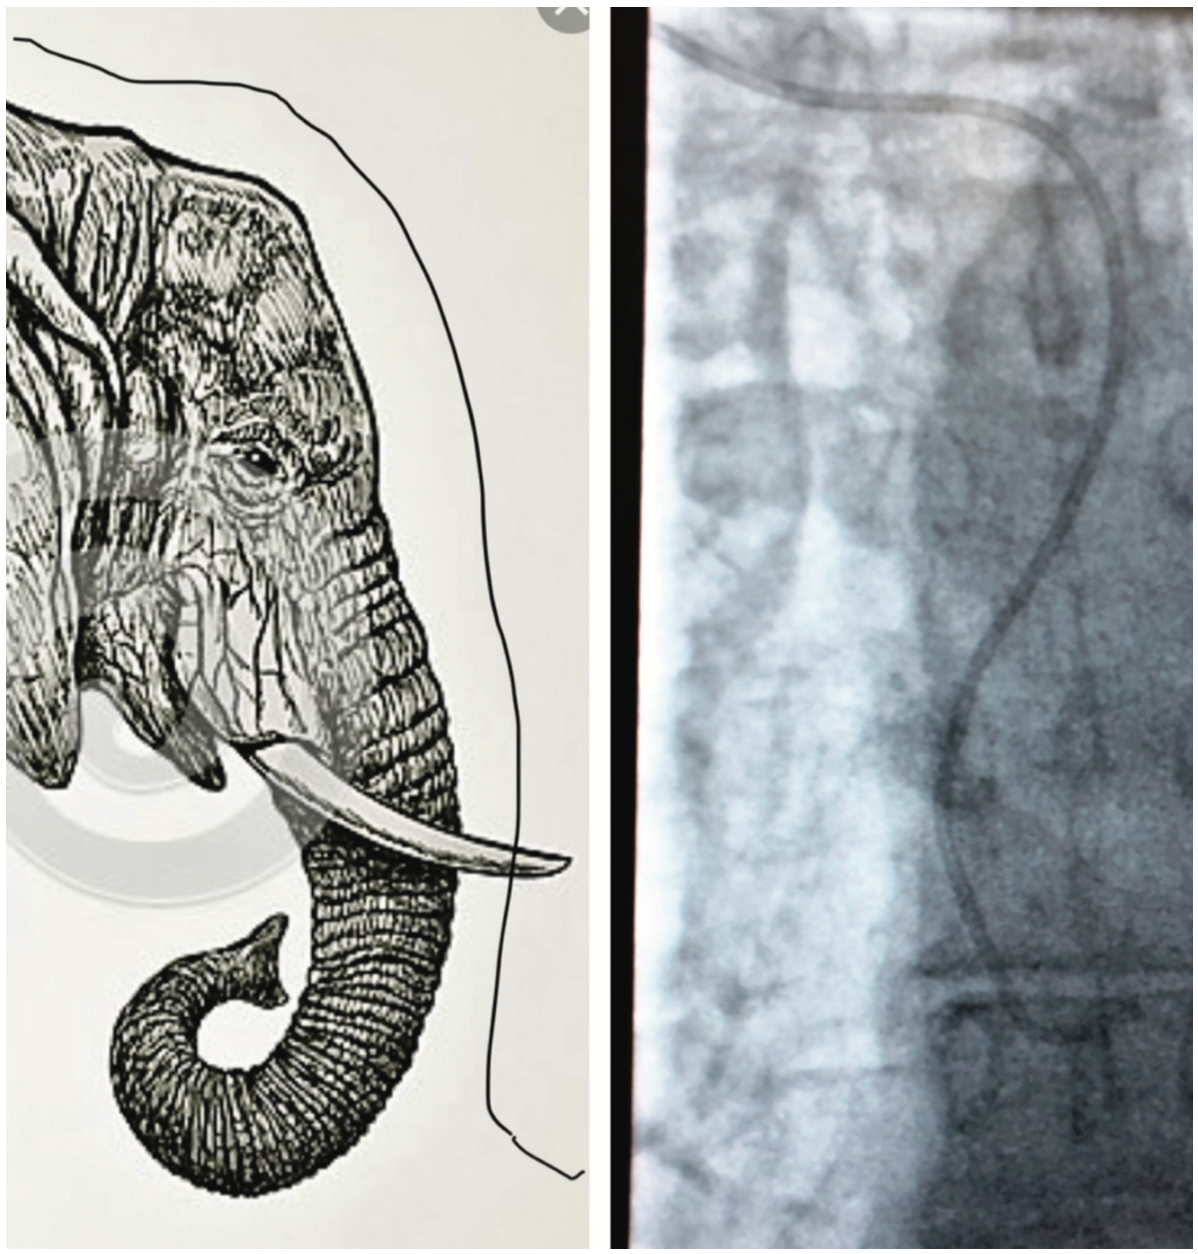

Radiographically, when encountering right subclavian tortuosity, catheters for the most part cross to the left side of the trachea, and can have an “S”-shaped rounded curve or resemble the profile view of an elephant’s head (Figure 2A). Right subclavian tortuosity in and of itself can make an easy procedure difficult and laborious. Encountering an aberrant right subclavian amplifies the difficulties further. Patients with an aberrant subclavian done from the radial approach are shown to only have a procedural success rate of 60%,3 although this source from Valsecchi et al is somewhat antiquated and techniques dealing with tortuous anatomy have evolved significantly. However, an aberrant subclavian can still put a significant damper on a proceduralist’s day.